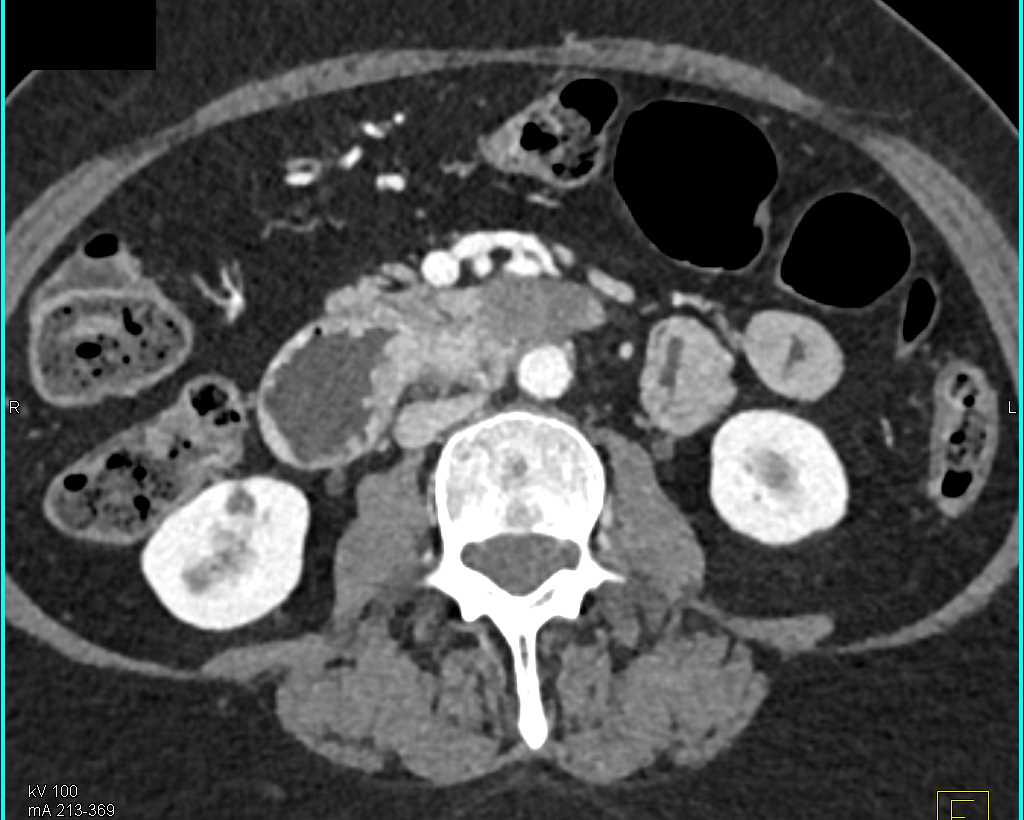

Duodenal Carcinoma with Obstruction